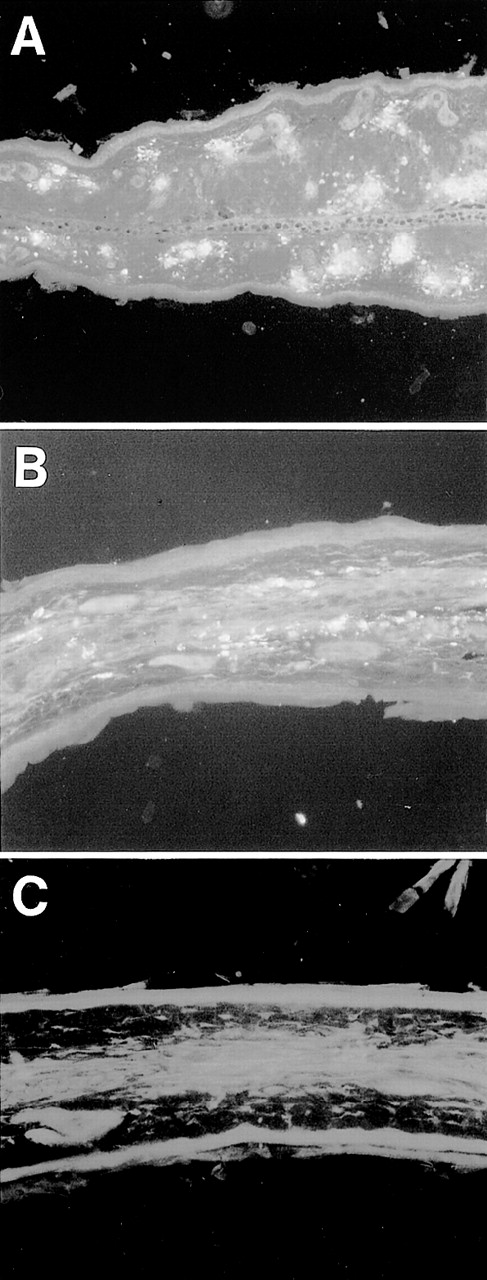

Esterase staining of skin of the ear. Ear skin tissues from wild-type and TNFβ−/− mice were fixed in formalin and sections were stained with naphthol AS-D chloroacetate, N,N′-dimethylformamide, and hexazotized new fuchsin, pH 6.3. Arrowheads indicate esterase-positive cells. Estimated numbers of mast cells were 16.4 ± 1.4/field and 18.1 ± 3.2/field, respectively.

Aggregation of FcεR or FcγR on mast cells leads to the rapid release of various mediators, including histamine, proteoglycans, and proteases from cytoplasmic granules, and to the induction of the synthesis and secretion of other mediators such as leukotrienes, prostaglandins, and platelet-activating factor (PAF) as well as a variety of cytokines, including TNF. Among these, leukotrienes, PAF, and TNF are possible candidates for mediators of leukocytoclastic angiitis, because they strongly induce PMN recruitment and the destruction of vessel walls. Among them, TNF turned out to be a crucial mediator, based on our finding that TNFαβ-deficient mice10 failed to develop skin vasculitis in this system despite the fact that some PMNs were observed in the ear section (Fig2D). On the other hand, these mice still developed glomerulonephritis similar to wild-type and FcRγ−/− mice (Fig 4D and Table 4). Staining of ear skin from wild-type and TNFαβ−/− mice with naphthol AS-D chloroacetate esterase exhibited similar distribution and number of mast cells in the tissue (Fig 6, see page3858). These results suggest that TNF is important for the effector phase of mast cells, but not for maturation or migration. To further establish the critical role of TNF in the induction of vasculitis, particularly in relationship with mast cells, BMMC from TNFαβ-deficient mice were transferred subcutaneously into6-19–injected FcRγ−/− mice. We found that the transfer of BMMC from TNFαβ−/− mice also failed to induce skin vasculitis in 6-19–treated FcRγ−/− mice (Table 3). BMMC from TNFαβ−/− mice show a similar surface phenotype (FcεR+c-Kit+FcγRII/III+Mac-1−Gr-1−) to wild-type BMMC and also function similarly in terms of the release of β-hexosaminidase in response to FcεR cross-linking (Fig 5A and B). Furthermore, we found that BMMC release a higher level of TNF than macrophages in the early phase of stimulation through FcγR (Fig 5C). These data suggest that TNF released from mast cells upon stimulation via FcγRIII is the main mediator responsible for the pathogenesis of skin vasculitis.